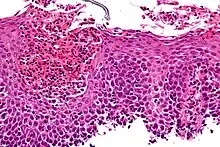

| An esophageal ulcer visualized by esophagoscopy: the reddened area at 10 o'clock on the surface of the mucosa. | |

Esophagitis can be diagnosed by upper endoscopy, biopsy, upper GI series (or barium swallow), and laboratory tests.[4]

An upper endoscopy is a procedure to look at the esophagus by using an endoscope. While looking at the esophagus, the doctor is able to take a small biopsy. The biopsy can be used to confirm inflammation of the esophagus.